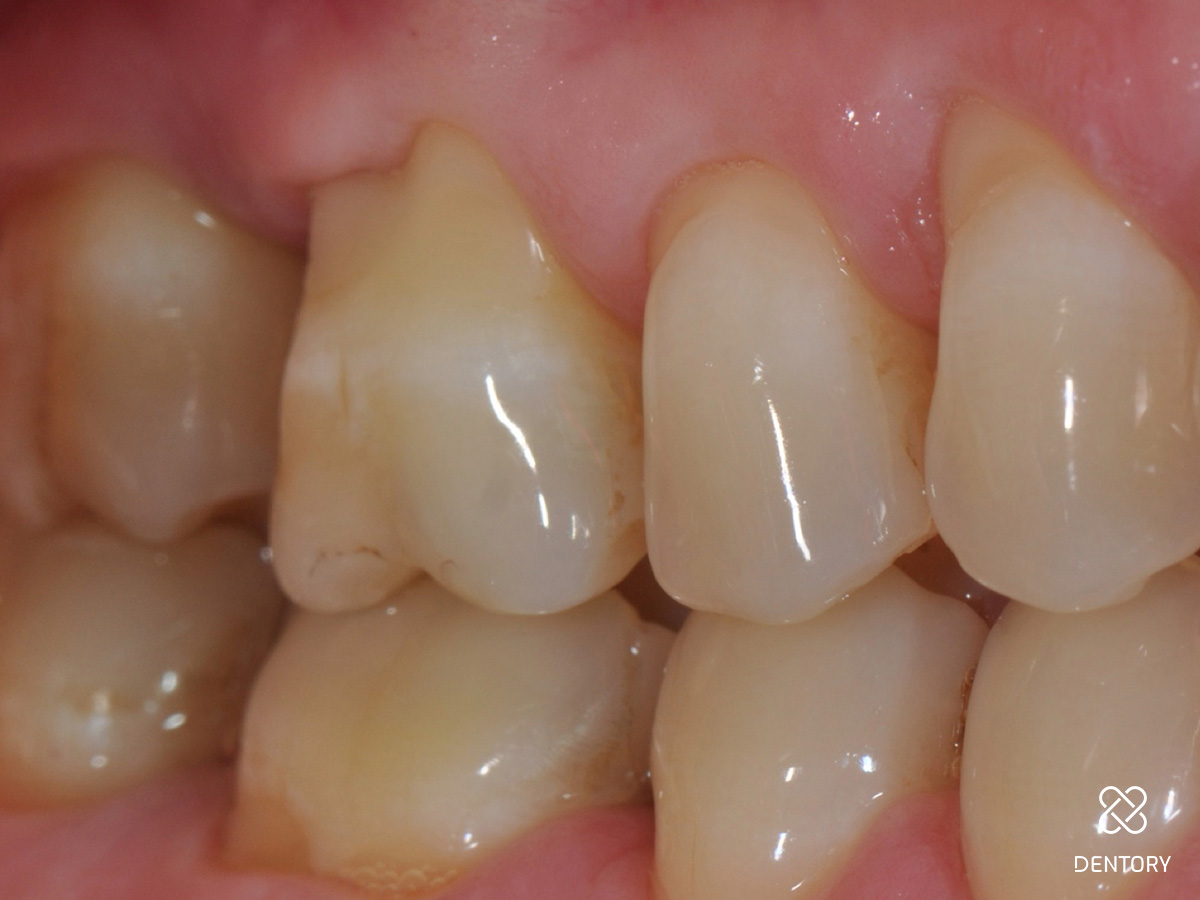

Abbildung 16

Die klinische Situation regio 16/17 sechs Monate nach Eingriff zeigt ein gesunde und stabile Gingivaverhältnisse.